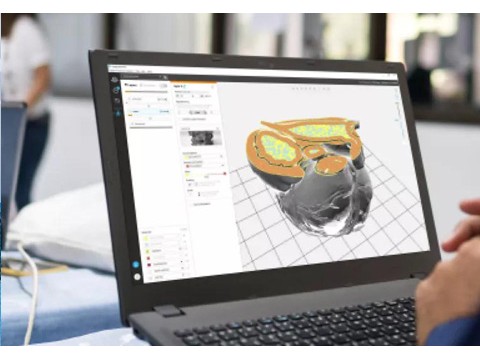

- 创新3D打印解剖模型软件,Stratasys持续推动个性化医疗发展

- Materialise软件+Stratasys硬件,超乎寻常的通用型医用3D打印系统?